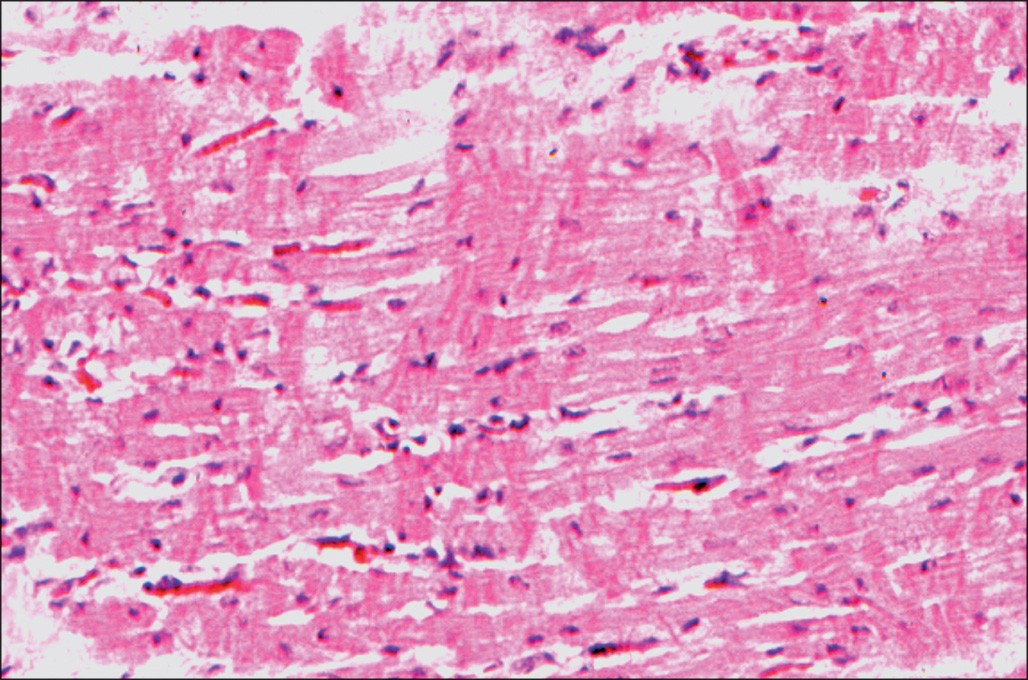

Despite the tachycardia and increased output common to patients with burn injury, structural lesions of the heart have been uncommon in our autopsies done on a pediatric population of patients. However, cardiac hypertrophy is a consistent finding at autopsy. Cardiac dilation and clinical evidence of poor myocardial contractility develop in some patients after burn injury. Bacterial endocarditis occurs in occasional patients with sepsis complicating burn injury. Nonbacterial thrombotic endocarditis (marantic endocarditis) has also been seen and may give rise to embolic complications ( Fig. 38.11 ). When the endocardial region of the left ventricle is examined at autopsy, small foci of necrosis associated with local hemorrhage are often observed ( Fig. 38.12 ). Contraction band necrosis is sometimes the only evidence of myocardial injury. These lesions may represent poor perfusion of a tissue with high metabolic demands during terminal episodes of hypotension. In some cases, they may represent the effects of endogenous or exogenous adrenergic agents. Rona and his associates have demonstrated that β-adrenergic agents, at high doses, stimulate the development of small foci of myocyte necrosis and hemorrhage in the subendocardial region of the heart. , This mode of injury is potentially preventable in burn patients.

This high-magnification micrograph of heart tissue shows the presence of multiple contraction bands in cardiac myocytes, seen as refractile dark red bands running across muscle fibers. This is an irreversible change that is seen early after ischemic injury causes lethal cell injury, especially when the tissue is reperfused with blood. It can also be seen in the setting of β-adrenergic toxicity. H&E stain.